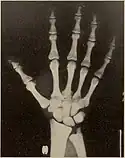

Pycnodysostosis causes the bones to be abnormally dense; the last bones of the fingers (the distal phalanges) to be unusually short; and delays the normal closure of the connections (sutures) of the skull bones in infancy, so that the "soft spot" (fontanelle) on top of the head remains widely open.[9] Because of the bone denseness, those with the syndrome suffer from fractures.[7]

Other abnormalities involve the head and face, teeth, collar bones, skin, and nails. The front and back of the head are prominent. Within the open sutures of the skull, there may be many small bones (called wormian bones). The midface is less full than usual. The nose is prominent. The jaw can be small. The palate is narrow and grooved. There will be delay in fall of milk teeth. The permanent teeth can also be slow to appear. The permanent teeth are commonly irregular and teeth may be missing (hypodontia). The collar bones are often underdeveloped and malformed. The nails are flat, grooved, and dysplastic. High bone density, Acro-osteolysis and obtuse mandibular angle are the characteristic radiological findings of this disorder.[10]

Pycnodysostosis is one of those disorders which has a typical facial gestalt[15] and can be clinically identified in the majority of cases. Skeletal surveys can also aid in clinical diagnosis and characteristic features include high bone density, acro-osteolysis and obtuse mandibular angle. Molecular testing will be the final resort to confirm the diagnosis. Due to the limited number of exons of the CTSK gene that causes pycnodysostosis, a cheaper genetic testing called Sanger sequencing can be employed to confirm the diagnosis.

Many of the radiological findings of PYCD are similar to those of osteopetrosis, a disease that causes bone density due to a defect in bone reabsorption; however, the two diagnoses differ in several ways.[17][18] In PYCD, there is also:[18]

- Hypoplasia or aplasia of the distal phalanges and ribs